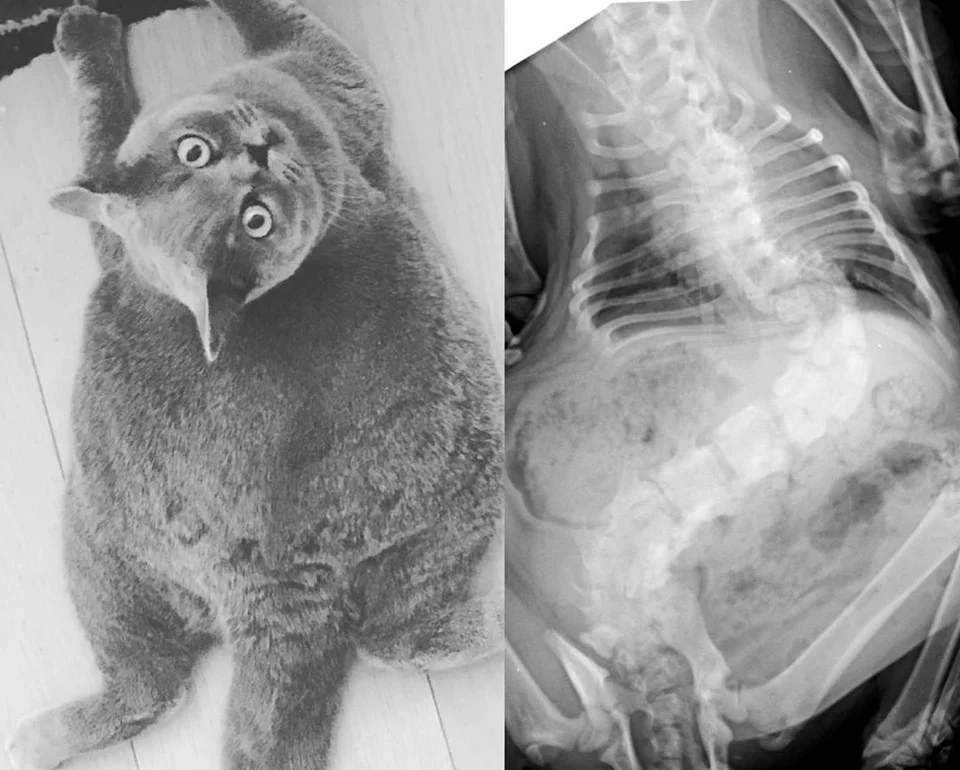

Gata redonda como una pelota de playa

La condición de Pitoe hace que su columna permanezca torcida y por tanto su apariencia es diferente a la de los demás gatos. Su cuerpo es más corto y ancho, lo que la hace parecer redonda.

Algunos problemas que se han presentado debido a la condición de la felina, son principalmente que ella no puede saltar como otros gatos y deben cuidar mucho su alimentación para evitar que tenga sobrepeso.

Además, una de sus patas traseras no es tan funcional, por lo que en ocasiones debe arrastrarse. Pero aun así, ella es muy feliz, saludable y amorosa.